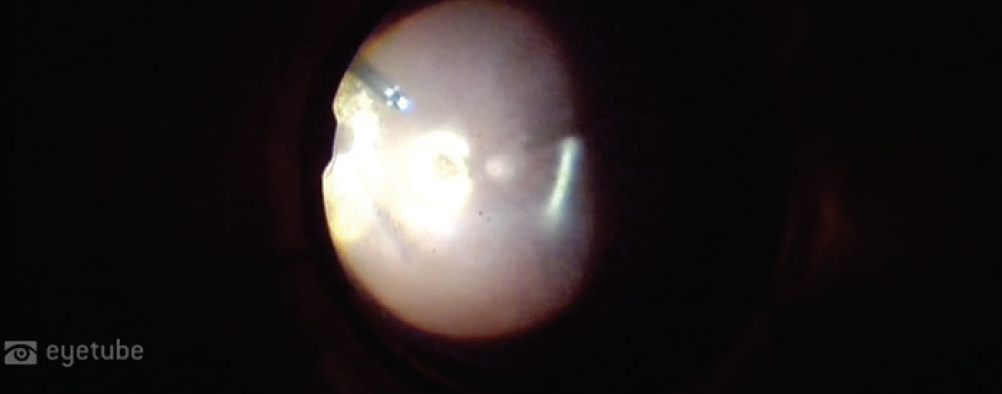

Case No. 3: Dexamethasone Intravitreal Implant 0.7 mg Under the Retina

From Federic Aissani, MD: A 70-year-old patient presented with a dexamethasone intravitreal implant 0.7 mg (Ozurdex, Allergan) under the retina. The patient’s surgical history included two surgeries for retinal detachment in the left eye and one surgery for retinal detachment in the right eye. I operated on the patient because the retina was detached; had the retina been attached, I would not have operated.

Commentary from Dr. Klufas: We have heard of steroid implant migration to the anterior segment in aphakic patients, but this one takes the cake. Consider the choices Dr. Aissani makes, including the decision to leave the implant in the eye.